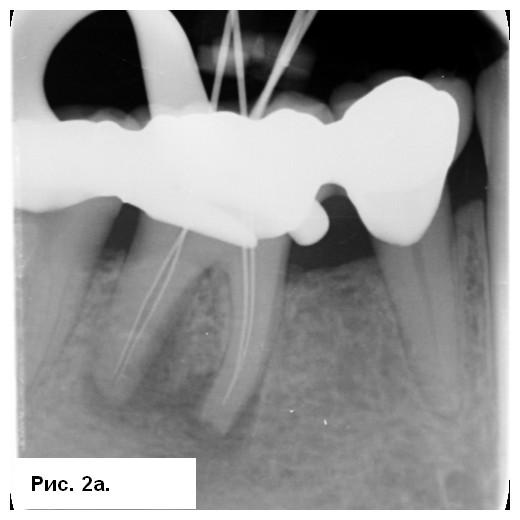

На рентгенограмме (рис. 1а) отмечались большие радиолюсцентые очаги на обоих корнях. Был поставлен диагноз: «некроз пульпы и острый апикальный абсцесс зуба 46». После консультации со стоматологом-ортопедом было принято решение провести эндодонтическое лечение с доступом к корневым каналам через существующую коронку. После вскрытия полости зуба было получено большое количество гнойного отделяемого с кровью (рис. 1b). Дренажу благоприятствовала ирригация 3 % NaOCl (рис. 1с), проведена инструментация корневых каналов системой 2Shape (MICRO-MEGA) и определена рабочая длина (рис. 2.а). Корневые каналы были заполнены гидроксидом кальция.